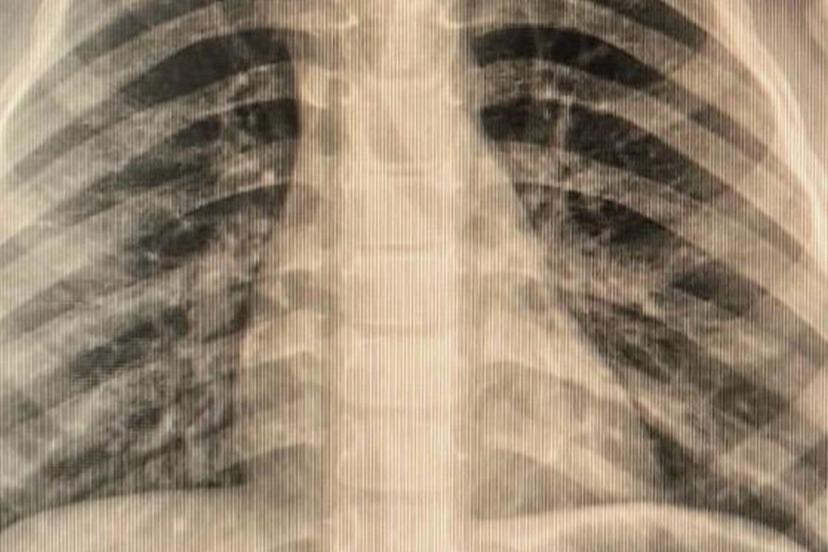

Çocuklarda sık karşılaşılan risklere değinen Özkaya "Günlük hayatta çocuklarda sık karşılaşılan yabancı cisim yutulması, kimyasal madde içilmesi ve solunum yollarına yabancı cisim kaçması önemli sağlık sorunları arasında yer almaktadır. Özellikle ilk üç yaşındaki çocuklar, yerde buldukları nesneleri ağızlarına götürme eğilimindedir. Madeni paralar, disk piller, iğneler ve küçük oyuncak parçaları çocuklar tarafından yutulabilmekte; bu maddeler yemek borusuna ya da solunum yollarına kaçabilmektedir. Bu tür durumlarda ailelerin olaya şahit olmaları hâlinde çocuğun ağzını kontrol etmeleri, yutma şüphesi varsa vakit kaybetmeden en yakın sağlık kuruluşuna başvurmaları gerekmektedir." dedi.

Solunum yollarına yabancı cisim kaçmasının da önemli bir risk olduğuna dikkat çeken Özkaya "Solunum yollarına yabancı cisim kaçması da günlük hayatta sık karşılaşılan ve hayati tehlike oluşturabilen durumlardan biridir. Özellikle üç yaşına kadar olan çocuklara çerez, fındık, fıstık, çekirdek gibi sert gıdaların verilmemesi gerekmektedir. Bu gıdalar solunum yollarına kaçarak ciddi nefes darlığına neden olabilmektedir. Böyle bir durumla karşılaşıldığında, mümkünse Heimlich manevrası uygulanmalı ve 112 Acil Servis eşliğinde en yakın sağlık kuruluşuna başvurulmalıdır. Bu tür vakaların operasyon gerektirebileceğine dikkat çekilerek, özellikle yemek borusunda kalan disk pillerin son derece tehlikeli olduğu vurgulanmaktadır. Disk piller, çocukta belirgin bir şikâyet olmasa bile kısa sürede yemek borusunda yanıklara ve delinmelere yol açabilmekte, hayati risk oluşturabilmektedir. Bu nedenle acil olarak ameliyathane ortamında çıkarılmaları gerekmektedir." şeklinde konuştu.